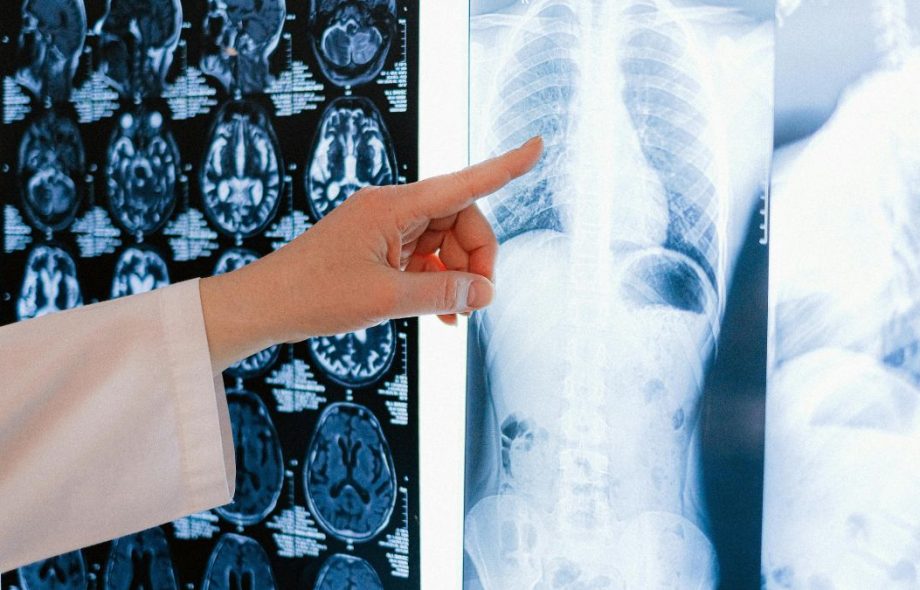

We use MRI scans to gather detailed images of the brain. Deep learning models are then trained to identify tumors based on thousands of these images. This reduces the chance of missing small or hidden abnormalities.

Deep learning makes it easier to find brain tumors by looking at MRI scans with unsurpassed speed and accuracy. It finds strange patterns and little changes in brain tissue that people might not be able to see. Our radiologists at SoCal Imaging and Open MRI use this cutting-edge technology to help them find malignancies earlier and with more confidence. This combination strategy cuts down on mistakes made by people, makes diagnoses more accurate, and makes sure that patients get the right care at the right time throughout important times in their health journey.

MRI or Magnetic Resonance Imaging is a non-invasive tool. It uses magnetic fields to produce clear detailed images of brain structures. MRI does not involve radiation which makes it ideal for repeated scans if needed.

MRI is especially good at showing soft tissue contrast. This means it can detect even small tumors, their exact location, and how they affect nearby areas.